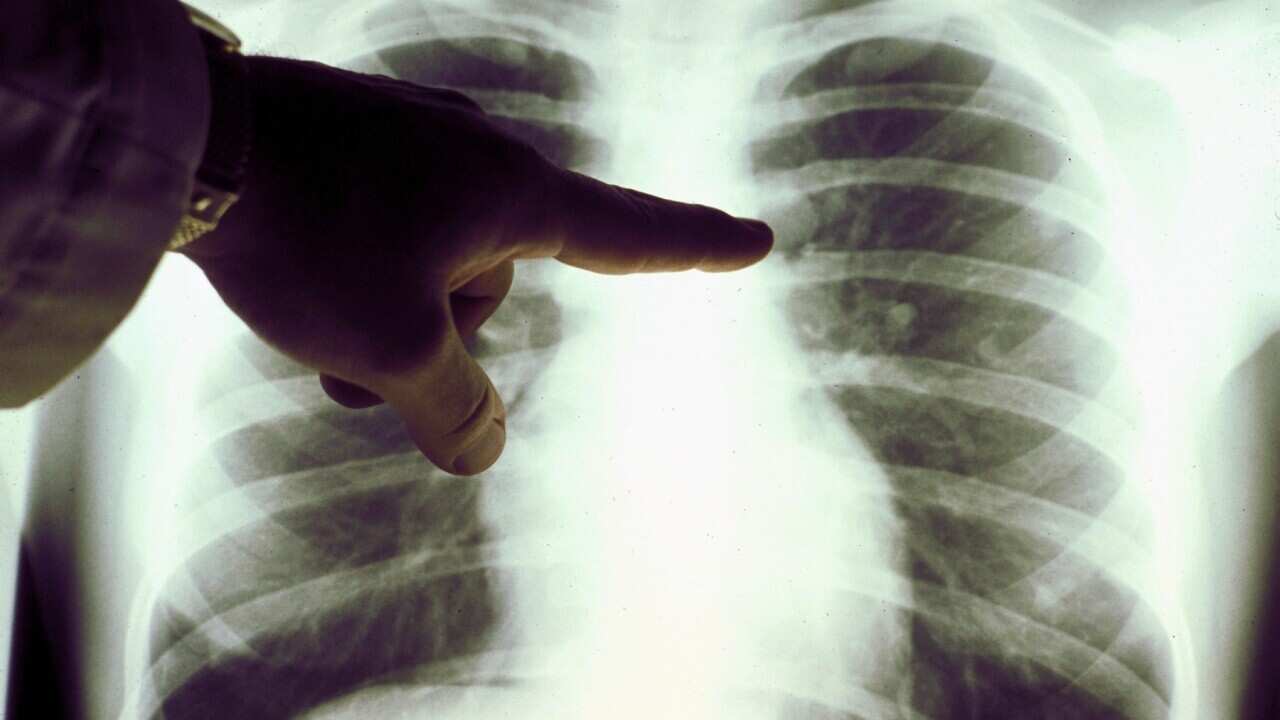

در نهایت وقتی وی بالاخره به پزشک مراجعه کرد، مبتلا به مرحله چهارم سرطان ریه تشخیص داده شد، که برای وی بسیار شوکه کننده بود.

این مخصوصا در مورد سرطان ریه که کشنده ترین سرطان استرالیا محسوب می شود اهمیت دارد.

بسیاری از علائم سرطان ریه، از جمله سرفه کردن، مشکل در نفس کشیدن و عفونت های سینه، شبیه علائم کروناویروس هستند.

به همین دلیل مرکز سرطان استرالیا یک راهنمای جدید منتشر کرده است تا متخصصان درمانی بتوانند این سرطان را در طول همه گیری کووید-۱۹ تشخیص دهند.

وی می گوید: «یکی از مشکلات مربوط به کووید-۱۹ این است که برخی از علائم کووید-۱۹ شبیه علائم سرطان های ریه هستند و به همین دلیل ما می خواهیم مردم توجه داشته باشند که سرفه یا عفونت سینه همیشه به دلیل کووید-۱۹ نیست.»